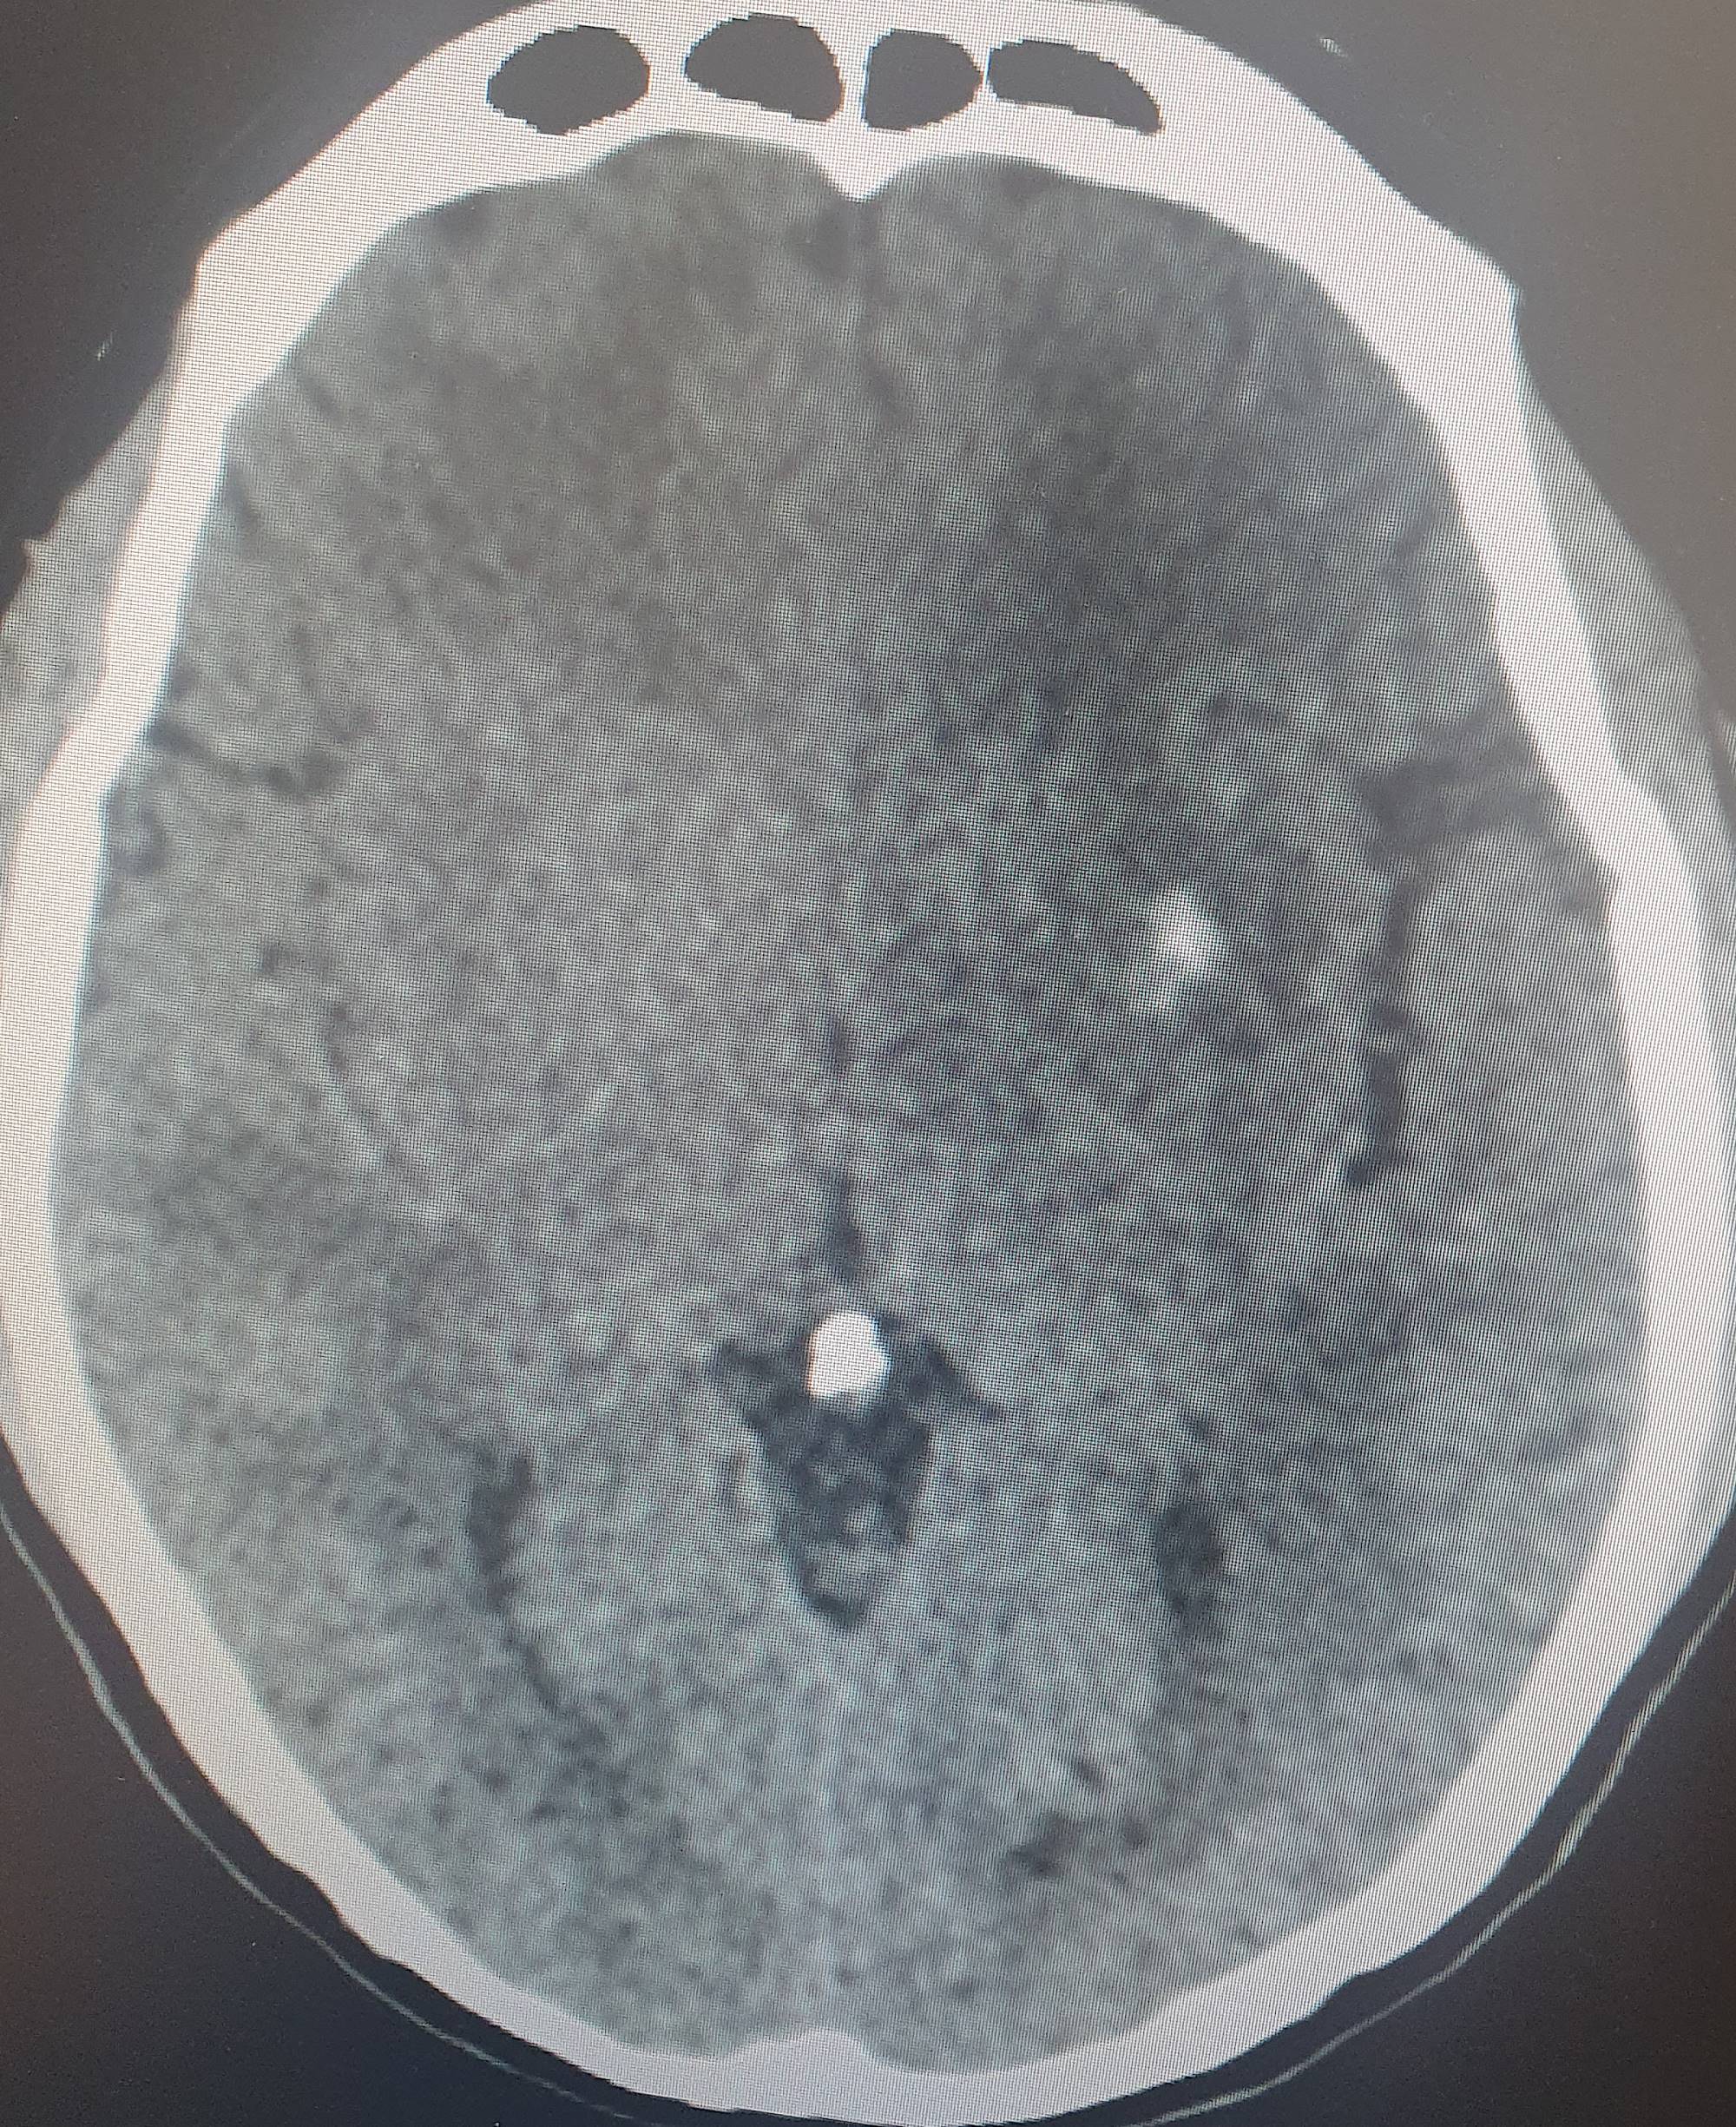

The average consultation time was 24.3 ± 14.4 hours, with extremes of 7 hours and 44 hours. Clinical presentations were headache (88.2%), visual disturbance (64.7%), disturbed consciousness (35.3%), epileptic seizures (23.5%) and motor deficit (29.4%) (Table 2). Mean systolic blood pressure was 190 ± 5.7 mmHg (extremes 150 - 24 mmHg), mean diastolic blood pressure 110 ± 5.1 mmHg (extremes 80 - 160 mmHg). Neuroradiological lesions (Figure 1) were edematous (88.2%), hemorrhagic (23.5%) and ischemic (11.7%). The topography of cerebral lesions was occipital (100%), parietal (82.3%), frontal (58.8%), temporal (47%), cerebellar (29.4%) and basal ganglia (23.5%) (Table 3).

Figure 1. Breakdown of cases by neuroradiological lesions.

Our findings on lesion topography (Figure 2 and Figure 3) are similar to those in the literature, which report that the parieto-occipital, frontal and temporal regions are most involved. More rarely, lesions may extend to the basal ganglia (14%), brain stem (13%) and splenium of the corpus callosum (10%) (Leroux et al., 2008). A normal CT scan does not exclude the diagnosis of PRES (Poma et al., 2014). Intracerebral hemorrhage is observed in 5% - 30% of PRES cases (Aracki-Trenkić et al., 2016; McKinney et al., 2012).

Figure 2. Bilateral occipital vasogenic edema.

Figure 3. Bilateral frontal-parietal-occipital edema with left lenticular hemorrhage.